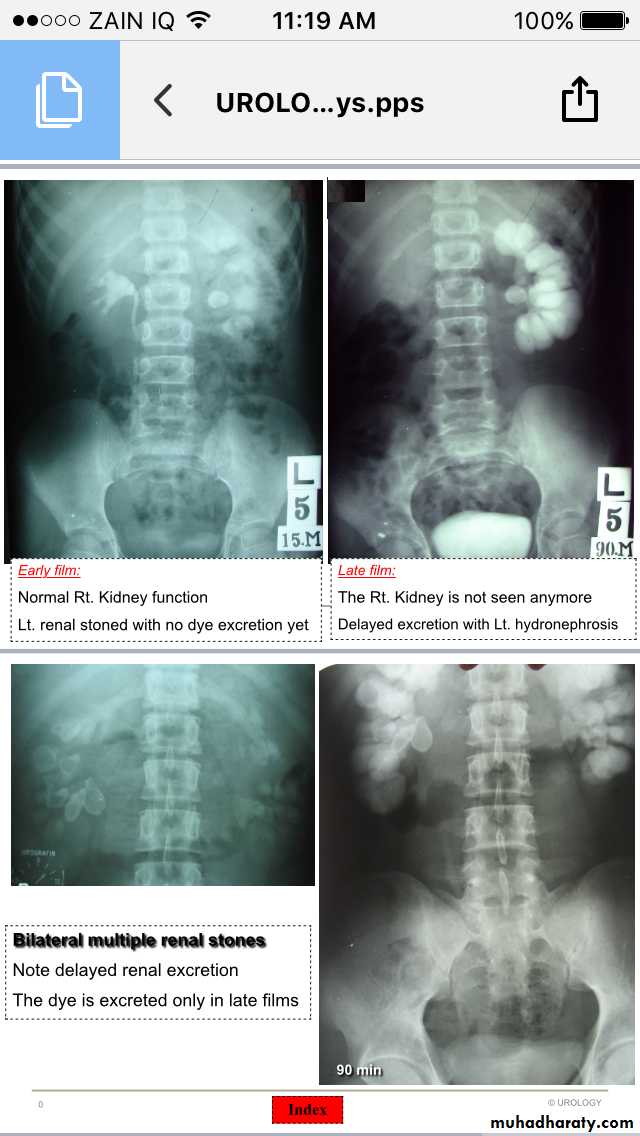

Renal stones

Ureteric stones